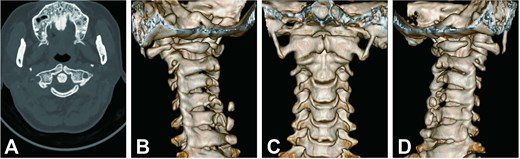

Cervical radiographs revealed hypoplasia of C1 but no evidence of atlantoaxial dislocation (Fig. 1). CT scans indicated bilateral bone abnormalities on the lateral sides of the posterior arch, particularly on the left side, with a midline cleft of the anterior arch (Fig. 2A). Three-dimensional reconstruction further demonstrated this abnormality (Fig. 2B–D). T2-weighted MRI revealed an intramedullary high signal at the C1 level, but no compression of the cord was observed (Fig. 3A and B). Cervical flexion-extension imaging indicated minor stenosis of the upper cervical spinal cord in the neck flexion position, but this alteration was not substantial (Fig. 3C–F). We considered that the high signal may be related to the repeated subtle activity of the posterior atlantoaxial arch in the past over a long period of time.

Sagittal and axial T2-weighted MRI of the cervical spine. (A, B) Supine neutral position. (C, D) Supine neck flexion position. (E, F) Supine neck extension position.